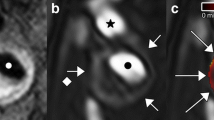

The images in Fig. 1 are from a symptomatic patient, with a 52% stenosis on the right side. The plaque contains a large intraplaque hemorrhage (IPH). Figure 1c shows the intra-luminal and adventitial signal change with time following contrast agent administration. Figure 2 is from the same artery and shows the multi-contrast MR images and calculated VVI. An ulceration can be clearly seen on the CE-MRA images, but is not so apparent on the 3D TOF-MRA. Surface irregularity can be observed in both pre- and post-contrast T1w images. The MR-DTI shows a large region of IPH. The VVI shows regions of high K trans around the ulceration and at the adventitia boundary, with a relatively low K trans inside the IPH, which is in agreement with a previous study [32].

a Shows DCE images at different time frames at a single slice location within an ICA branch of the plaque. The dashed red and green lines in frame 5 show the boundary of carotid lumen and adventitia. b Shows the corresponding black blood T1w image with red and green lines delineating the lumen and wall boundary. c Represents the mean signal intensity time course within the lumen (red) and adventitia (green)